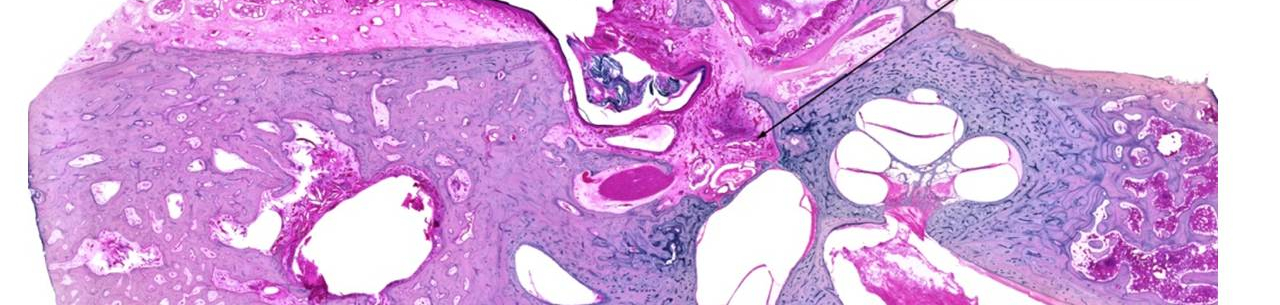

Hlavním tématem vlastního odborného programu byla problematika cholesteatomu. Jednotlivé přednášky byly již tradičně koncipovány jako odpověď na otázku co požadovat a co lze očekávat od jednotlivých odborníků v diagnostice a léčbě u chronického středoušního zánětu s cholesteatomem.

ORL lékaře na ambulanci (M. Černý), pacienta (I. Bártová), rentgenologa (J. Dědková), patologa (J. Laco), vyšetření chuti (J. Vodička), klasifikačních systémů (V. Chrobok), chirurga – otolaryngologa (L. Školoudík), vestibulologa (M. Stříteská), statistické analýzy (T. Valenta), sluchové protetiky (J. Dršata).